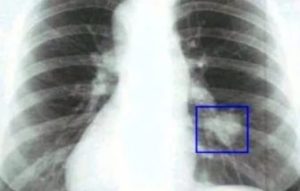

При рассмотрении рентгеновского снимка с патологией можно заметить затемненное пятно

При рассмотрении рентгеновского снимка с патологией можно заметить затемненное пятно. Это и есть опухоль. Внешний вид образования может различаться в зависимости от формы заболевания, его течения, стадии развития и многих других факторов. При описании полученного снимка врач уточняет локализацию теней.

Выглядит рак на рентгеновском снимке как затемненное пятно. Внешний вид злокачественных опухолей может быть различным в зависимости от формы заболевания, стадии ее развития и других факторов. Составляя описание, врач обращает внимание на локализацию теней. По этому признаку заболевание определяется как центральный или периферический, перибронхиальный или бронхоальвеолярный тип.

Полезно знать! Дифференцировать доброкачественные и злокачественные новообразования можно по характеру контура. Независимо от формы опухоль снимке имеет форму пятна с неравномерными, расплывчатыми очертаниями.

Рентген легких при подозрении на карциному не всегда является достоверным, поскольку он может демонстрировать только затемнение или осветление тканей органа. Рак легких на рентгене возможно обнаружить в форме кругообразного воспаленного участка.

На рентгенограмме при первичном обследовании врач может заметить малые области потемнения, не имеющие ровных очертаний.

Как правило, на снимках сбоку, обозначается точное расположение области заражения. В случае, когда очаг поражения находится на задней стенке легкого, то такое злокачественное образование будет выглядеть как темное пятно со рваными краями.

Наличие опухоли на задней стенке легких Периферическая форма рака Полостная форма рака